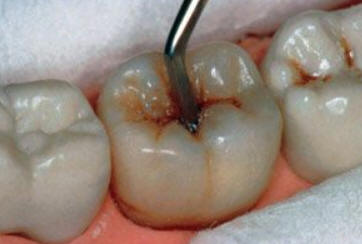

Una morfología de la fisura estrecha, con forma de botella de "Coca-Cola" genera un nicho ecológico ideal para la colonización de cualquier bacteria productora de ácidos. Al no poder remover en forma períodica dicho biofilm de una zona tan estrecha, el ataque ácido genera una lesión cariosa en la dentina, con un aspecto de esmalte intacto a la inspección visual, o sea un típico código 3 y 4 de ICDAS Completo. (Caries Moderada para el ICDAS COMBINADO)

Código 3 (Caries moderada) in vitro. Los códigos 3 in vivo debe ser sellado para evitar el avance del proceso carioso. (MNO)

Código 4 (Caries moderada) in vitro. Los códigos 4 in vivo deben ser tratados en forma operatoria con preservación dental (MOPD), porque presentan dentina infectada.